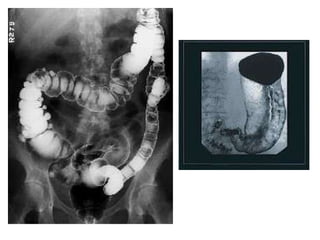

Digital  spot film images and photospot images may be acquired by using the same  digital   fluoroscopy  system.  Individual frames from a  digital   fluoroscopy  sequence can be stored  digital ly and can be used instead of conventional spot film and photospot images.  Digital  photospot images will have the same characteristics (eg, resolution) as  digital  fluoroscopic images.

Digital spotfilm images and photospot images may be acquired by using the same digital fluoroscopy system. Individual frames from a digital fluoroscopy sequence can be stored digital ly and can be used instead of conventional spot film and photospot images. Digital photospot images will have the same characteristics (eg, resolution) as digital fluoroscopic images.